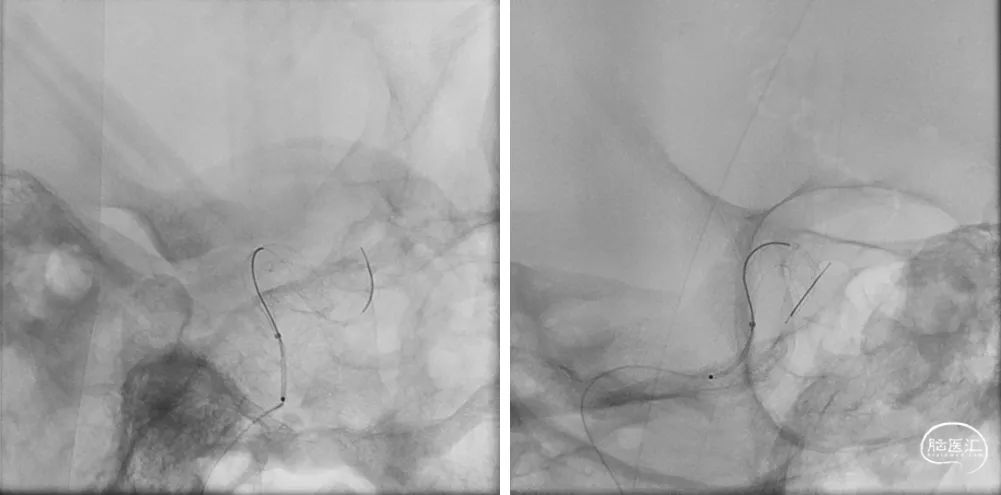

释放支架头端,远端锚定后,确认支架远端释放,贴壁良好,缓慢采用推挤方式将支架释放。

支架成功释放后,造影显示动脉瘤瘤颈支架覆盖贴壁良好,右侧颈内动脉通畅,右侧颈内动脉及分支血管显影良好,无血栓。

术中快速CT扫描未见颅内出血,支架贴壁良好。